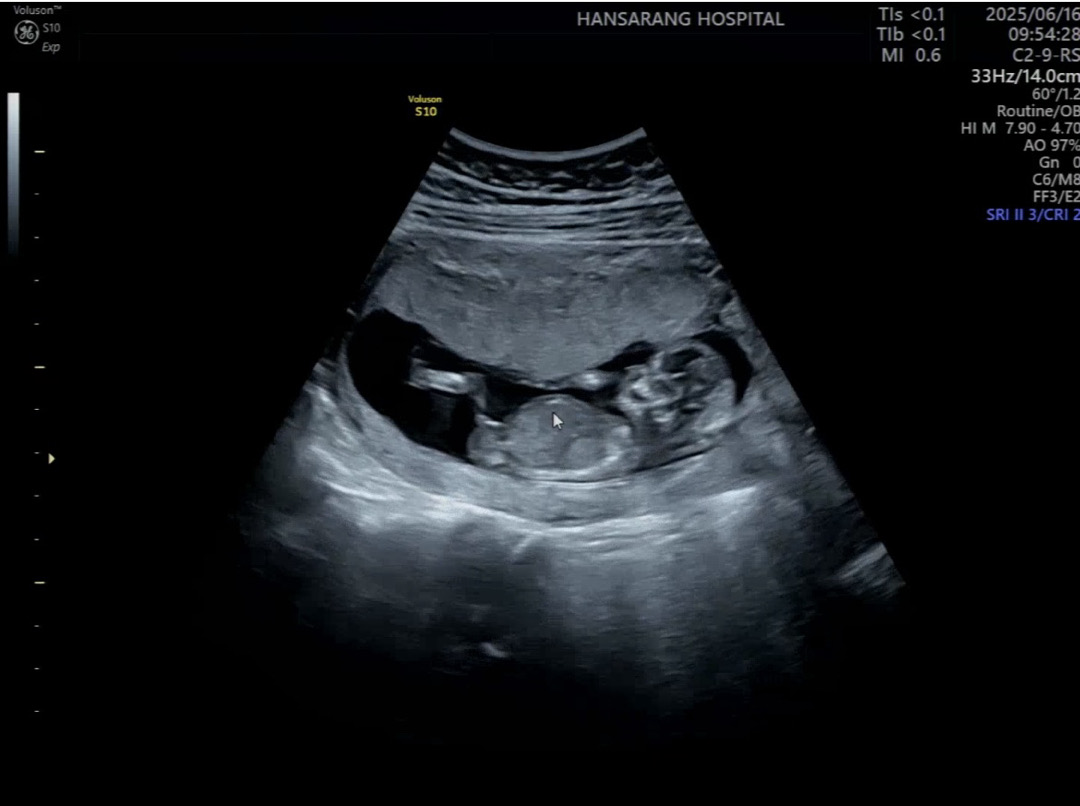

딸이네용

2025년 12월 베동

각도법 보이나요??

각도법 이사진으로 보이나요?

딸 같아요